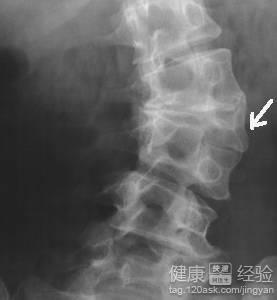

1隱形脊柱裂的病症通常會造成脊椎錯位或者脊椎接位不正常,這樣會使泌尿系統紊亂,造成孩子的心理自己生理不正常,但是家長的安慰是非常重要的,保持孩子良好的心態更加有利於孩子的治療,如果能不做手術的話盡量不要做。

2孩子在生長發育期由於缺鈣或者鈣質吸收不進去,或者在孕婦懷孕時自己缺少鈣造成腰間的骨頭發育不好,然後脊背出現了小裂縫,這是常見的一種現象,這種情況一般患者隨著年齡增長逐漸就自愈了,是不需要去治療的,